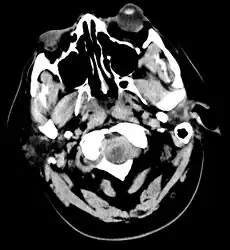

.jpg.webp)

The modality of choice is computed tomography (CT scan), without contrast, of the brain. This has a high sensitivity and will correctly identify 98.7% of cases within six hours of the onset of symptoms.[28][4] A CT scan can rule out the diagnosis in someone with a normal neurological exam if done within six hours.[29] Its efficacy declines thereafter, and a lumbar puncture is also recommended.[1][4] Magnetic resonance imaging (MRI) is more sensitive than CT after several days.[5]